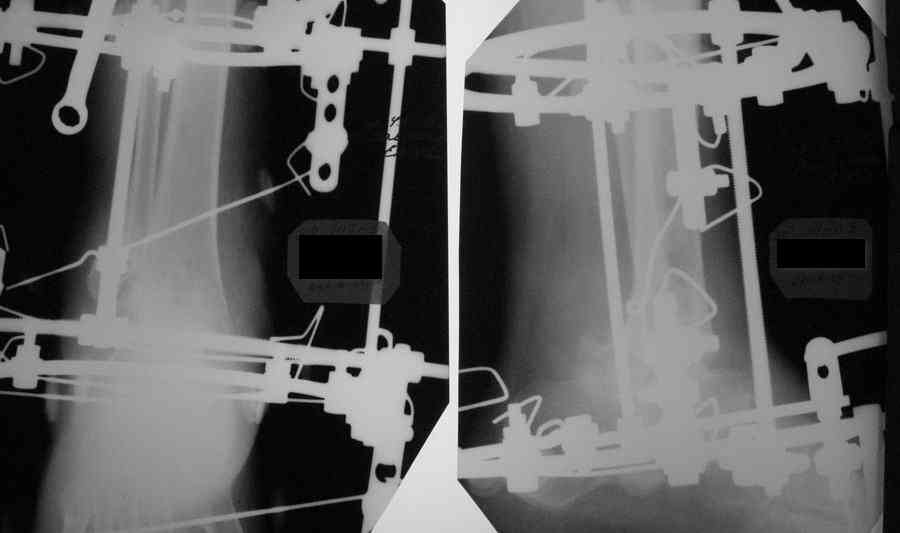

Александр Николаевич! Постарался переделать рентгенограмму - не знаю лучше ли стало- снимки никудышные:(

Смещение стопы кзади видно более отчетливо. Это намеренно так сделано, поскольку так сформировались контактные поверхности?

И как оценить, насколько эти старания состоятельны? В любом случае, при артродезе голеностопного сустава фиксация пятки

избыточна.

>Смещение стопы кзади видно<> более отчетливо. Это намеренно так сделано,поскольку так сформировались контактные поверхности?

В Campbell`s рекомендуется смещение тарана чуть кзади (чуть- цифры нет), но контакт действительно в таком положении получился максимальным, хотя, я думаю, тоже можно постепенно переместить, если это критично.

You want to have your heel as posterior, especially when the contact is better, but also for good lever (Ri4ag) for the gastroc complex.AL